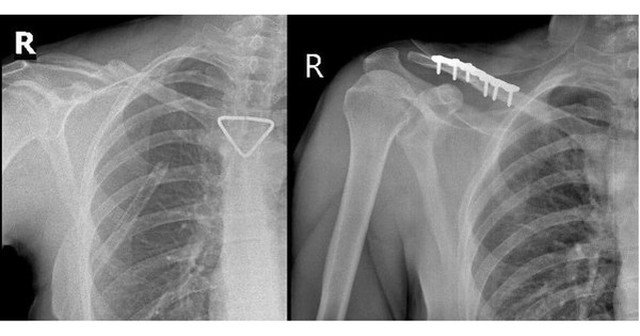

Qua hội chẩn liên chuyên khoa và đánh giá của bác sĩ gây mê hồi sức, người bệnh đủ điều kiện an toàn để thực hiện phẫu thuật kết hợp xương đòn phải bằng nẹp vít. Ca mổ do ê-kíp BSCKII Trần Văn Dương và BS Phạm Ngọc Huy thực hiện, diễn ra thuận lợi. Nẹp vít được đặt vững chắc, trục xương phục hồi giải phẫu tốt.

Thêm 1 du khách người Nga được bác sĩ cấp cứu kịp thời- Ảnh 2.

Hình ảnh Xquang trước và sau mổ. Nẹp vít được đặt vững chắc, trục xương phục hồi giải phẫu tốt